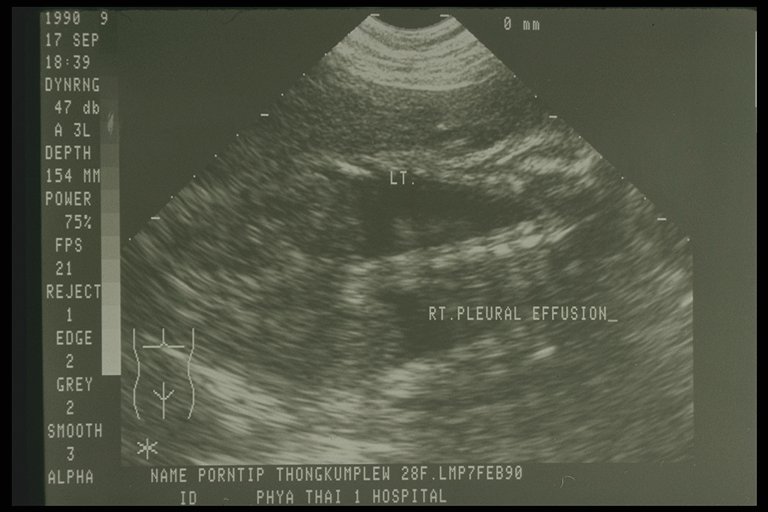

Prenatal ultrasonography showed bilateral congenital chylothorax, massive pleural effusion was detected in both chest cavity